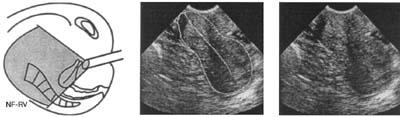

Рис. 8. NF-RV. Нонфлексио-ретроверзио. Перегиба тела матки нет — заднее наклонение шейки.

Если эндометрий и эндоцервикс образуют одну прямую ось (NF, см. табл. 2; рис. 7—9) или угол, открытый кзади (RF, см. табл. 2; рис. 4—6), проведение катетера в полость матки не представляет затруднений. Обычно сложности в проведении катетера возникают при наличии переднего угла между эндоцервиксом и эндометрием (положение AF, см. табл. 2; рис. 1—3), причем чем меньше этот угол, тем сложнее проведение катетера.